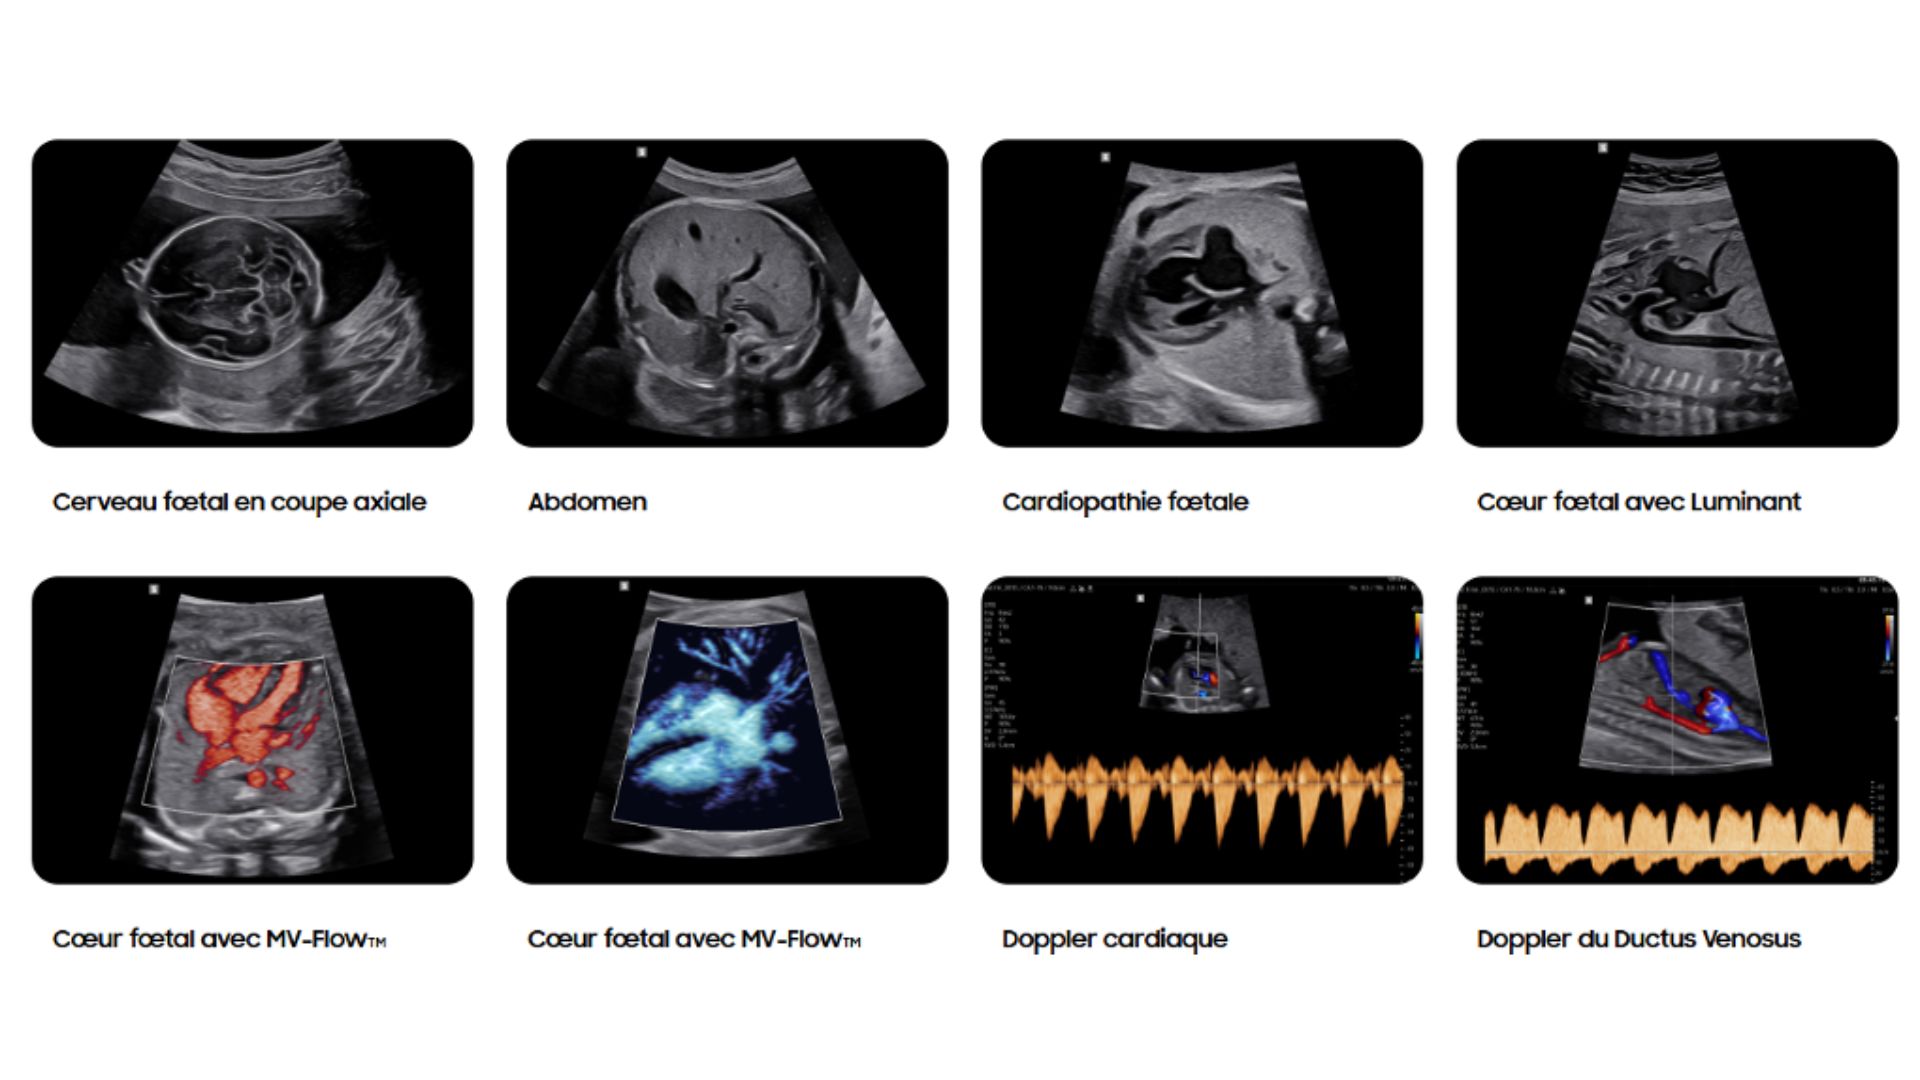

MV-Flow™ offre une nouvelle alternative au Doppler Énergie pour visualiser les flux lents et la microvascularisation des structures. Les hautes cadences images et les filtres d’imagerie avancés permettent au MV-Flow™ de coder le mouvement des hématies en s’abstenant des artefacts de l’imagerie B et ainsi améliorer la résolution spatiale.

LumiFlow™ est un codage de visualisation avec un effet tridimensionnel qui permet d’étudier l’architecture des vaisseaux, de manière intuitive.

Luminant™ est un algorithme de différenciation structurelle qui transforme les contours d’une image 2D et améliore l’analyse des structures, comme pour le cœur ou le cerveau fœtal.

L’outil HeartAssist™, basé sur la reconnaissance d’images, permet d’identifier les structures de l’image échographique afin de réaliser automatiquement les mesures nécessaires à l’analyse du cœur fœtal. Il génère ensuite des résultats précis, ainsi que le tracé des courbes de normalité.